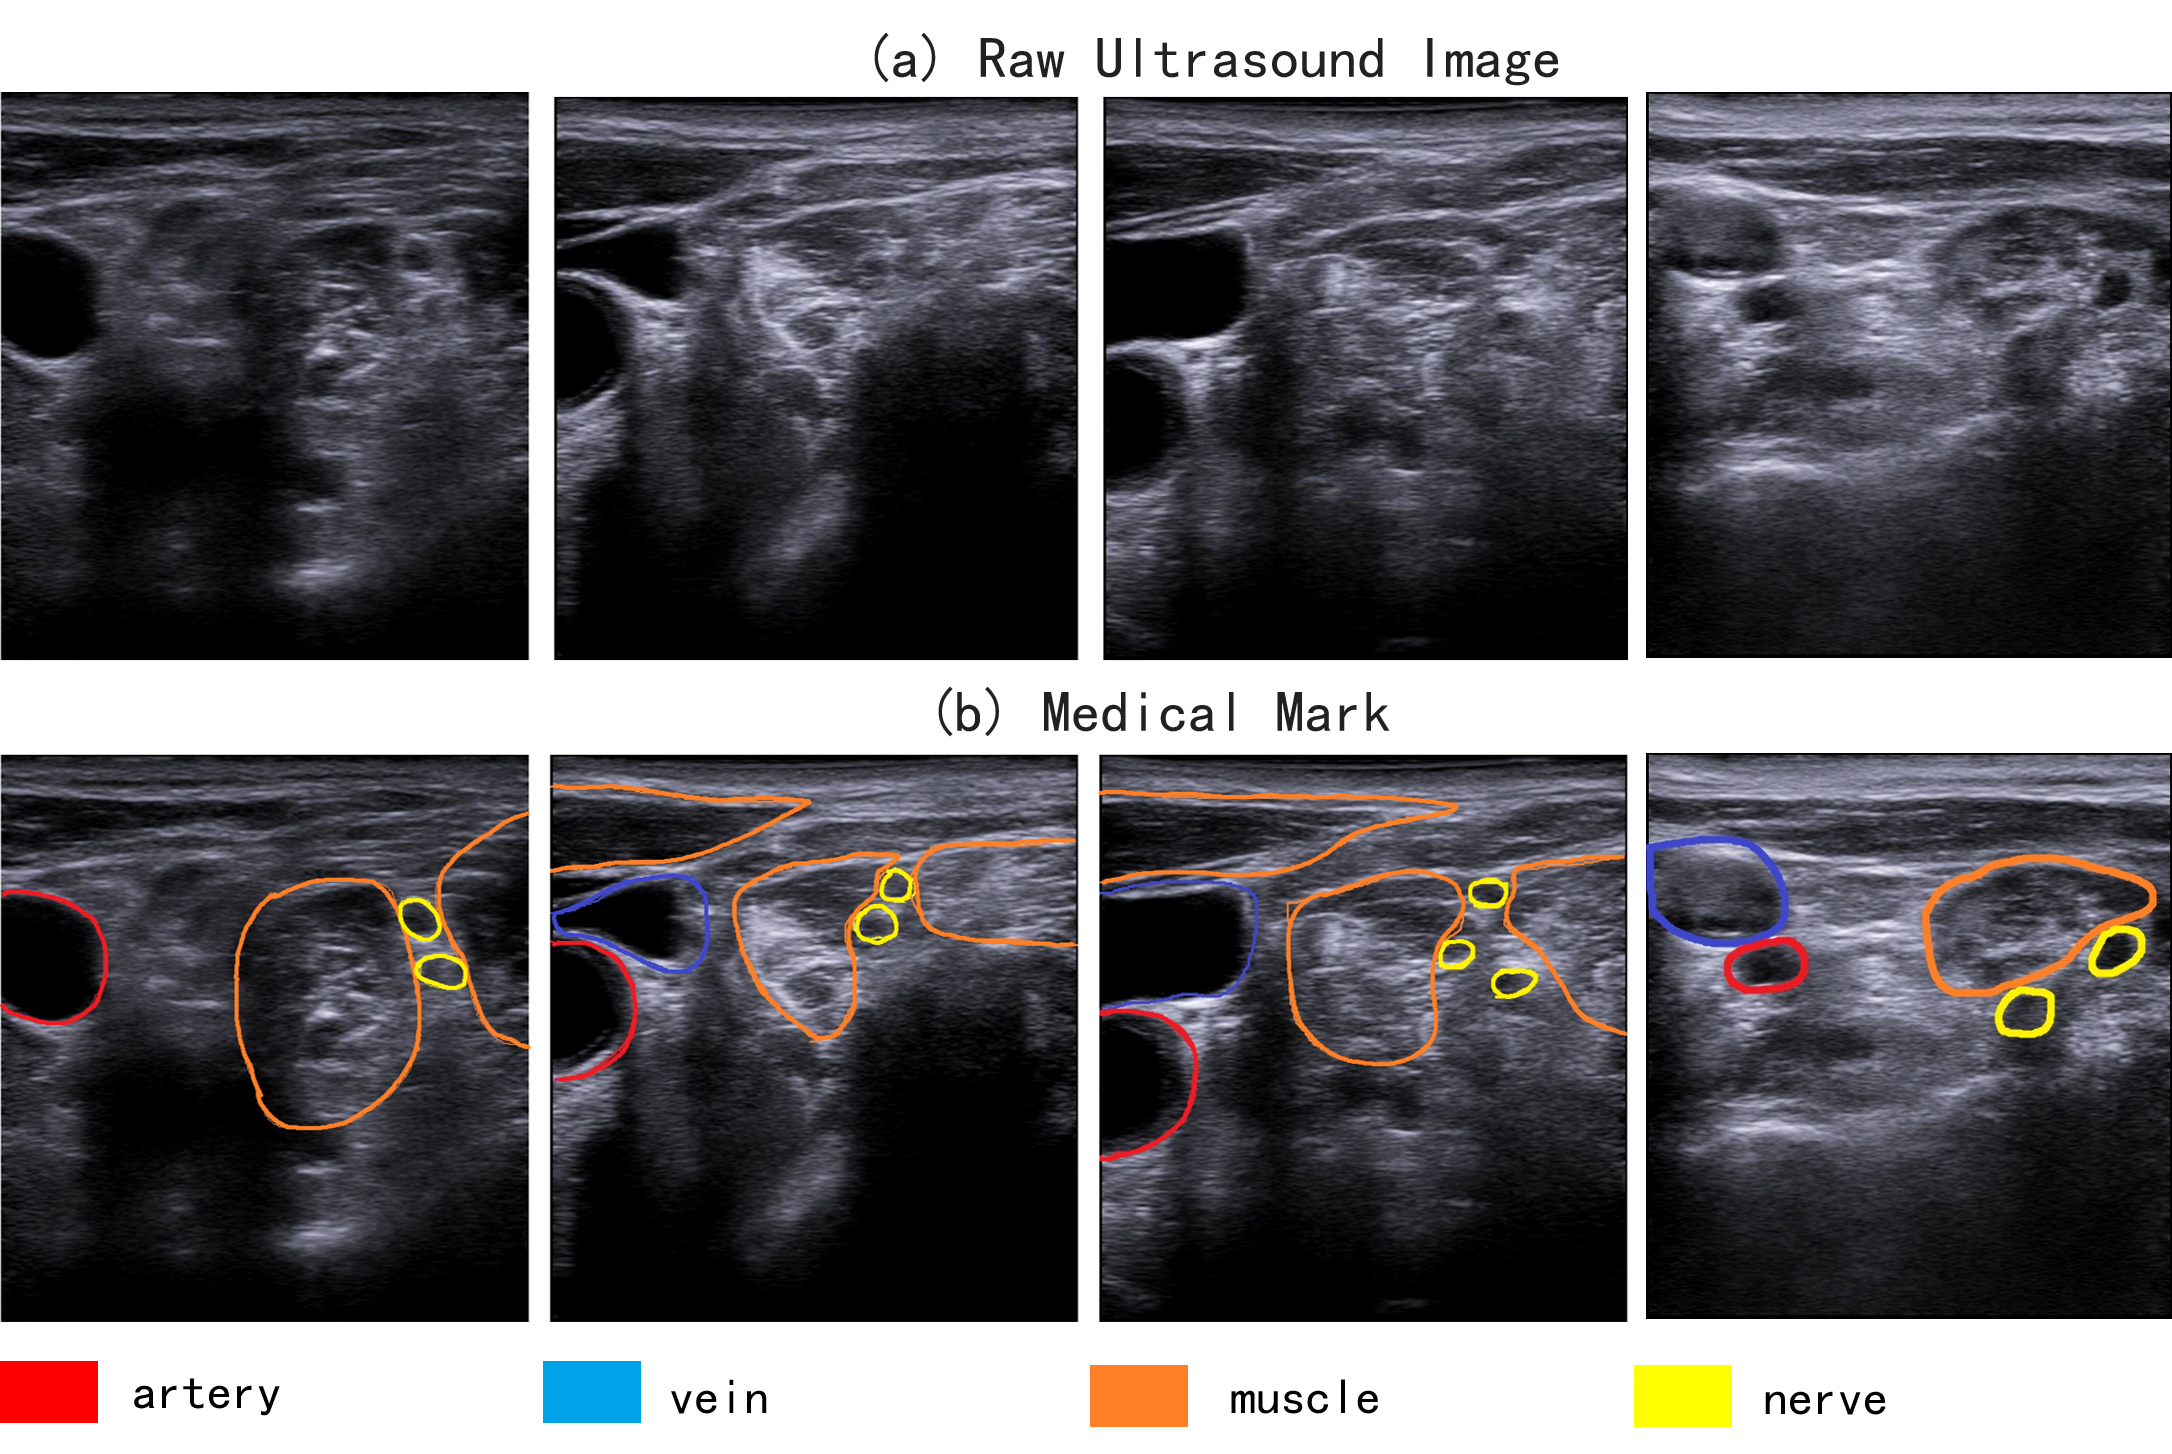

Each ultrasound image contains targets and their corresponding annotated masks. The Labelme [36] is adopted for manual labeling, and the ground truth labels are marked by the anesthesiologists. Part of the masks and images in UBPD are shown in Figure 1, there are 4 categories including nerve, muscle, vein, and artery. These tissues varies in shape and size, and have different characteristics. The vein and artery are salient in ultrasound imaging, and their edges are clear and large in size. On the contrary, the size of nerve is small, and it is inconspicuous.

During the labeling process, anesthesiologist has concluded that the nerve has the following characteristics: bright edges, dark in internal, its diameter is within 3mm, and it is continuous beaded or honeycomb. In clinical practice, the anesthesiologist will first identify the arteries and veins, then identify the muscle, and finally the nerve. The target recognition process of the anesthesiologists is consistent with their examination procedures in clinical anesthesia.

There are two types of contrast features adopted in the segmentation task: spatial contrast and local contrast feature. The spatial contrast refers to the contrast between large regions, and it reveals the global and semantic information of the image. The local contrast refers to the contrast between smaller regions. For salient objects (e.g. artery and vein in Figure 1 (b)), they have clear edges, large shapes and other histology features. In addition, they are more sensitive to the semantic information and more advantage in segmentation task [22]. However, the advantages of salient objects result in the challenge for segmenting the inconspicuous and small objects. When aggregating features of different scales using upsampling and element-wise sum, the features of pixels in inconspicuous objects will be dominated by the features of salient objects. Some information of inconspicuous objects would be ignored in the final prediction, resulting in incorrect labeling for pixels at certain locations. For nerve segmentation task, the size of objects is across a large range of scales, and it is important to consider both spatial and local contrast features. Therefore, the Spatial Local Contrast Feature (SLCF) is proposed to effectively aggregate spatial and local contrast features.